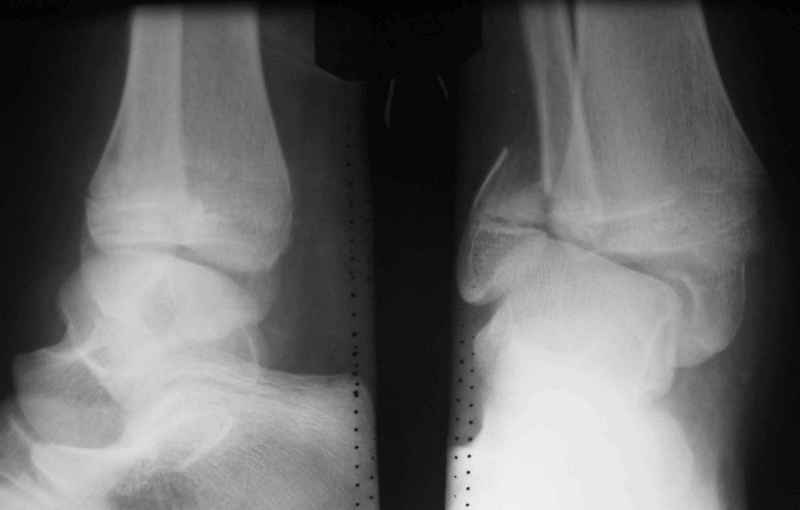

Здравствуйте, коллеги.Обратились родители мальчика 15 лет. Сами врачи.В июле 2009 года - перелом лодыжек.

Лечили спорно, на мой взгляд. В результате - - сращение наружной лодыжки с укорочением, подвывих голеностопа кнаружи (вальгус) в итоге компенсаторно передний отдел стопы ставит на варус. Нагрузку ограничивает.

Снимки в приложении.

С этой целью предлагаем восстановить анатомию м/берцовой кости, следствием чего будет возможность выставить центр тарана по оси голени, устранить эквинус и суппинацию переднего отдела стопы.